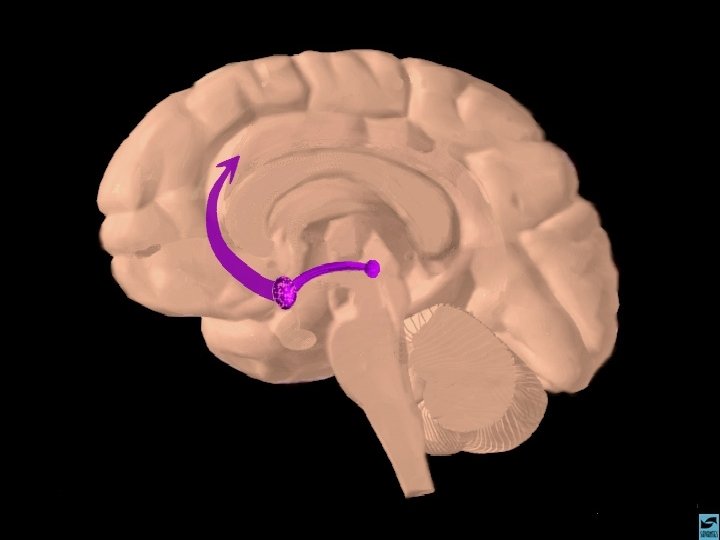

MACONHA TETRAHIDRO CANABINOL EFEITOS CEREBRAIS 1 - DISTRIBUI-SE RAPIDAMENTE POR TODO O CÉREBRO 2 - TEM AFINIDADE COM O RECEPTOR FORMADO AMANDAMIDA, QUE EXISTE NO HIPOCAMPO, TRONCO CEREBRAL E TRATO PÁLIDO 3 - AGE COMO NEUROMODULADOR ALTERANDO A PRODUÇÃO DE UM SEGUNDO MENSAGEIRO REGULADO POR OUTRO NEUROTRANSMISSOR